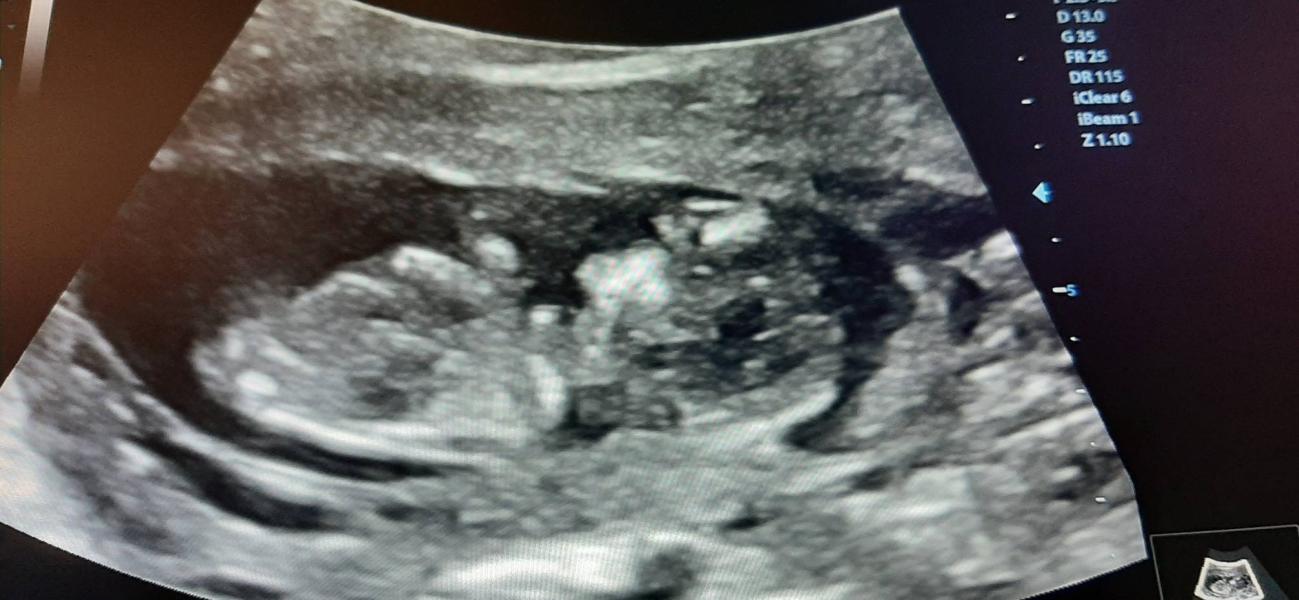

Сходила на первый скрининг.

Только нашли кисту довоььно большую...

послушала сердечко❤😍

Так и проходит беременность, от узи до узи

Когда видишь и знаешь что все с человечком хорошо.